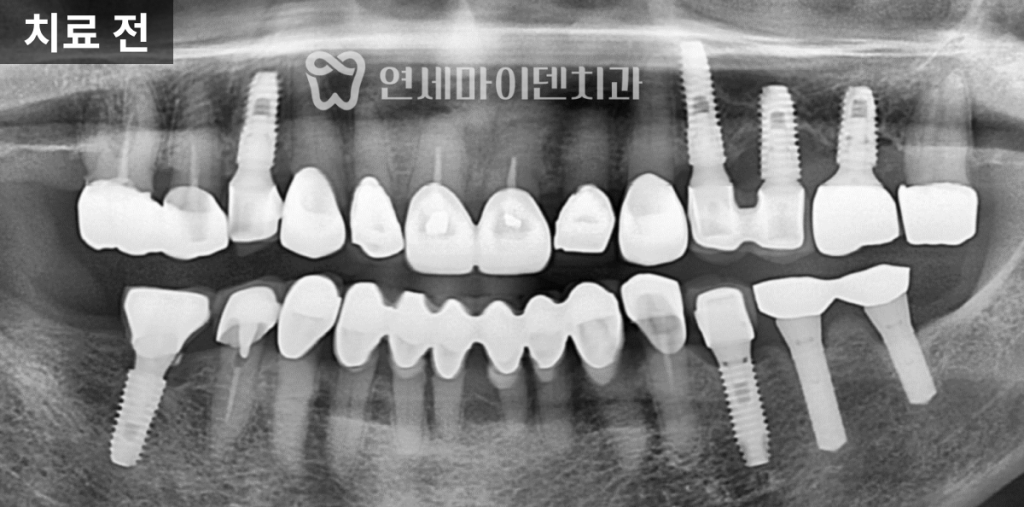

저희 병원에 재치료를 받으러 오신 사례입니다.기존 임플란트 실패 원인 분석

이 환자분은 한 달 전에 타원에서

임플란트를 식립 받으셨지만,불과 한 달만에 임플란트가 빠져서

저희 병원을 찾아오셨습니다.구강 내 상태를 확인하고

CT 촬영을 진행한 결과,

해당 부위는 골밀도가 낮았고

염증이 완전히 해소되지 않은 상태였습니다.또한 기존에 시행된

뼈이식 재료 역시

안정적으로 정착되지 못한 모습이

확인되었습니다.이러한 상황이라면

처음부터 발치 즉시 임플란트를

진행하기보다는,감염 부위를 충분히 제거하고

치조골 회복을 유도한 뒤

안정적인 환경에서 식립을 고려했어야 합니다.

또 하나 주목할 점은

픽스처 위에 힐링 어버트먼트가

이미 연결된 상태였다는 점입니다.고정력이 충분히 확보되지 않은 상태에서

힐링 어버트먼트를 연결하면

픽스처에 지속적인 힘이 전달되고,

이로 인해 임플란트 실패로

이어질 가능성이 높아집니다.실제로 이 케이스에서는

픽스처가 단단히 고정되지 않은 상태였고,

결과적으로 식립 후

한 달 만에 임플란트가 탈락하게 되었습니다.임플란트 재수술 과정